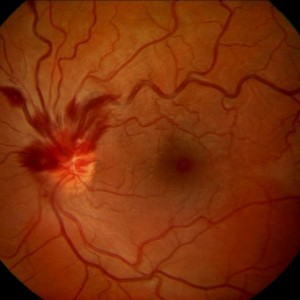

Hemizentralvenenverschluss (اختصارات و إقتصارات: Hemi-ZVV)

| الإنجليزية | hemi-central retinal vein obstruction (اختصارات و إقتصارات: HRVO, HCRVO) |